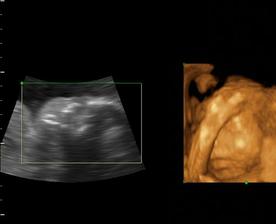

Naša maličká Emka alebo Silvinka...🙂

Od 19. júna 2008, teda od 21. týždňa vieme, že sa nám na 99% narodí dievčatko...na mene neodznela ešte úplná zhoda, preto Ema alebo Silvia...no ja dúfam, že sa mi podarí presadiť Emu, aj keď Silvia je tiež krásne meno...🙂...